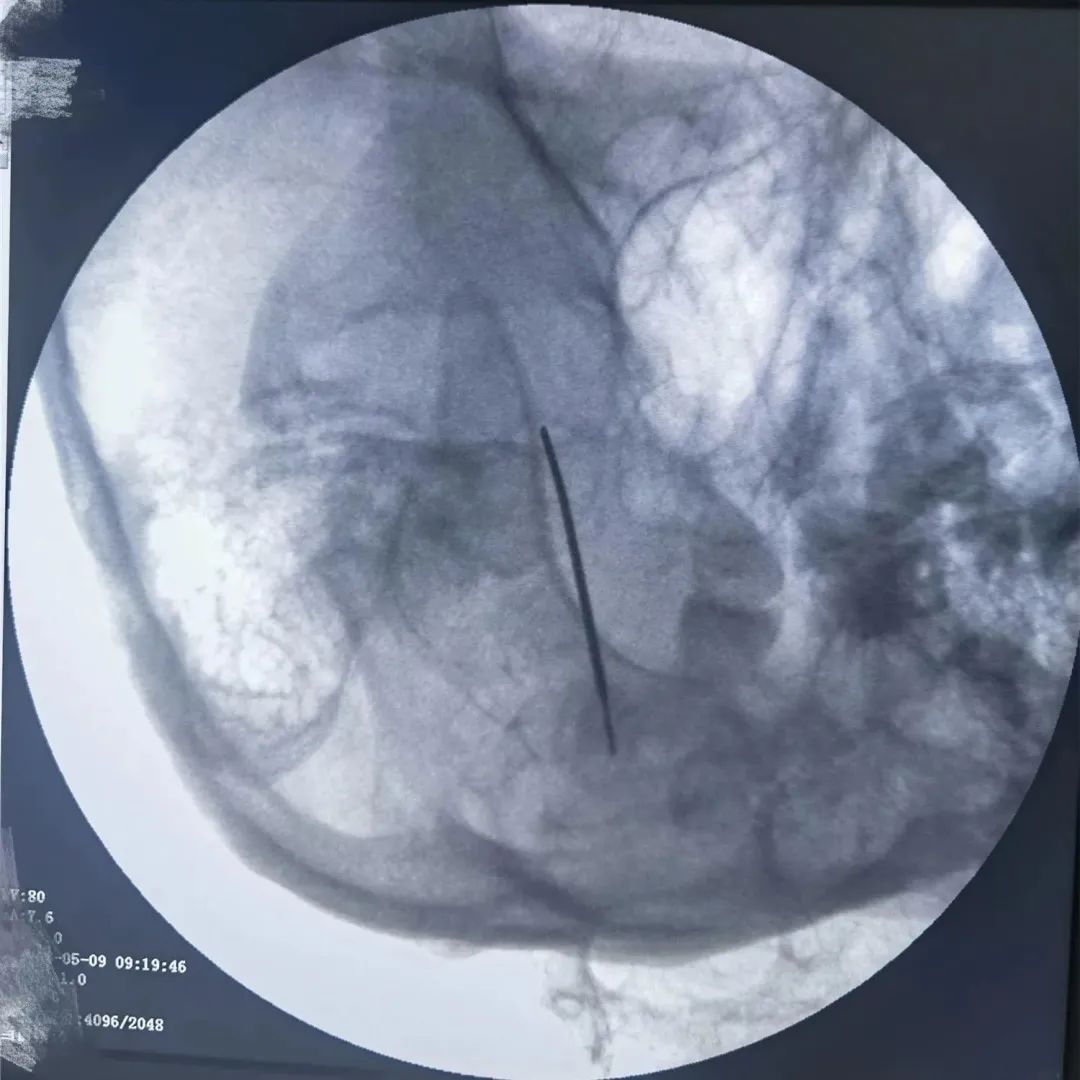

當(dāng)藥物治療的療效減退或者出現(xiàn)患者無(wú)法耐受的藥物不良反應(yīng)而導(dǎo)致藥物治療失敗時(shí),可以盡早考慮外科手術(shù)治療。半月神經(jīng)節(jié)射頻消融術(shù)是近年來隨著疼痛醫(yī)學(xué)的發(fā)展而逐漸發(fā)展并日趨成熟的一門技術(shù),該治療方法成功率高、創(chuàng)傷小,并發(fā)癥少、風(fēng)險(xiǎn)小、費(fèi)用低,是目前治療三叉神經(jīng)痛比較先進(jìn)且見效快的方法。

經(jīng)過疼痛康復(fù)科李加威副主任詳細(xì)問診及相關(guān)檢查后,鑒于患者的病情比較頑固,決定為其進(jìn)行三叉神經(jīng)痛射頻熱凝術(shù)。治療過程中病人處于清醒狀態(tài),且無(wú)明顯不適。治療及康復(fù)過程都很順利,出院時(shí)患者未再有發(fā)作性疼痛,精神狀態(tài)明顯好轉(zhuǎn)。